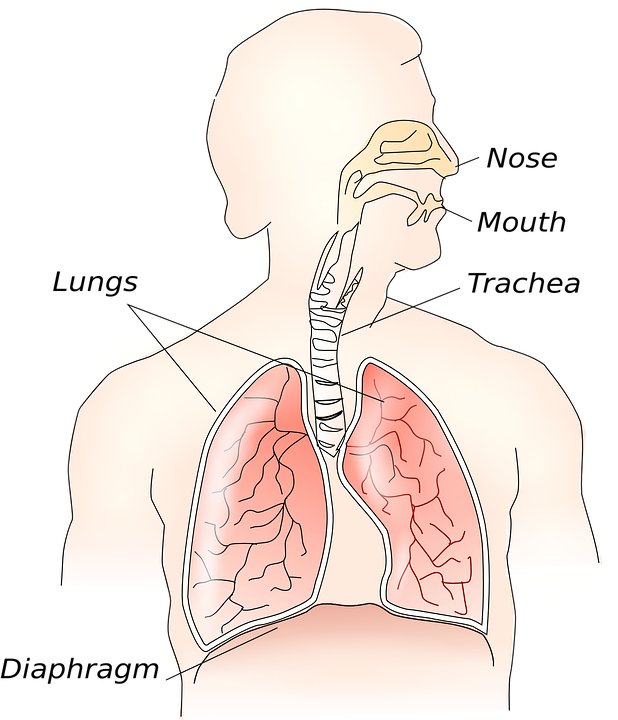

24. May Prevent Asthma

Asthma represents a public health problem and traditionally is classified as an atopic disease, where the allergen can induce clinical airway inflammation, bronchial hyperresponsiveness, and reversible obstruction of airways. R

Both CB1 and CB2 receptors are involved in lung protection. R

The activation of CB1 receptors on bronchial nerve endings has bronchodilator effects by acting on the airway smooth muscle and may be beneficial in airway hyperreactivity and asthma. R